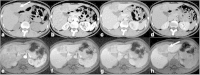

Malignancies of the biliary tract include cholangiocarcinoma, gallbladder cancers and carcinoma of the ampulla of Vater. Biliary tract adenocarcinomas are the second most common primary hepatobiliary cancer. Due to their slow growing nature, non-specific and late symptomatology, these malignancies are often diagnosed in advanced stages with poor prognosis. Apart from incidental discovery of gall bladder carcinoma upon cholecystectomy, early stage biliary tract cancers are now detected with computed tomography (CT) and magnetic resonance imaging (MRI) with magnetic resonance cholangiopancreatography (MRCP). Accurate characterization and staging of these indolent cancers will determine outcome as majority of the patients' are inoperable at the time of presentation. Ultrasound is useful for initial evaluation of the biliary tract and gallbladder masses and in determining the next suitable modality for further evaluation. Multimodality imaging plays an integral role in the management of the biliary tract malignancies. The imaging techniques most useful are MRI with MRCP, endoscopic retrograde cholangiopancreatography (ERCP), endoscopic ultrasound (EUS) and positron emission tomography (PET). In this review we will discuss epidemiology and the role of imaging in detection, characterization and management of the biliary tract malignancies under the three broad categories of cholangiocarcinomas (intra- and extrahepatic), gallbladder cancers and ampullary carcinomas.